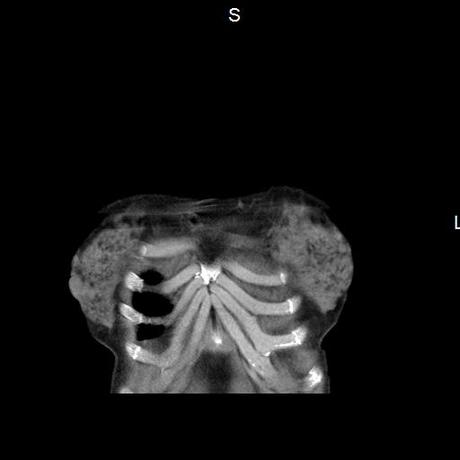

Se realiza volumen de tórax en fase simple, desde los opérculos torácicos hasta los hemidiafragmas, observándose:

El parénquima pulmonar con areas parcheadas difusas en vidrio despulido combinadas con otras areas hipodensas de baja atenuación debidas a atrapamiento aéreo y engrosamiento intersticial y zonas de fibrosis de predominio en lóbulos medios e inferiores de ambos pulmones.

- LOS HALLAZGOS PUEDEN ESTAR EN RELACIÓN A NEUMOPATIA INTERSTICIAL PROBABLE ETIOLOGIA HIPERSENSITIVA VS AUTOINMUNE/BACTERIANA/FUNGICA.